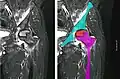

In the early stages, bone scintigraphy and MRI are the preferred diagnostic tools.[18][19]

Nuclear magnetic resonance of avascular necrosis of left femoral head. Man of 45 years with AIDS. -